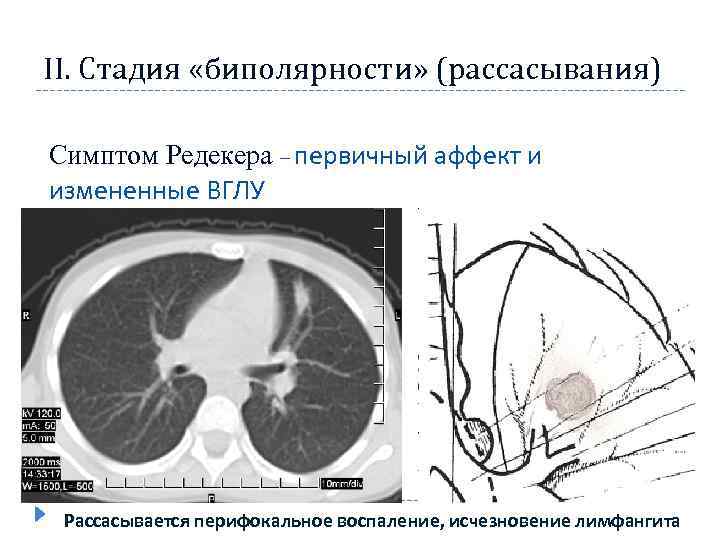

II. Стадия «биполярности» (рассасывания) Симптом Редекера – первичный аффект и измененные ВГЛУ Рассасывается перифокальное воспаление, исчезновение лимфангита

II. Стадия «биполярности» (рассасывания) Симптом Редекера – первичный аффект и измененные ВГЛУ Рассасывается перифокальное воспаление, исчезновение лимфангита

Рентгенологические признаки в стадию рассасывания и уплотнения ПТК постепенное исчезновение перифокальной инфильтрации в лёгочной ткани и перинодулярной инфильтрации в области корня лёгкого лёгочный компонент обычно представлен ограниченным затемнением или фокусом средней интенсивности, лимфатические узлы — расширением и деформацией корня лёгкого. размеры лёгочного компонента и поражённого корня лёгкого продолжают уменьшаться; постепенно в них обнаруживают признаки кальцинации 16

Рентгенологические признаки в стадию рассасывания и уплотнения ПТК постепенное исчезновение перифокальной инфильтрации в лёгочной ткани и перинодулярной инфильтрации в области корня лёгкого лёгочный компонент обычно представлен ограниченным затемнением или фокусом средней интенсивности, лимфатические узлы — расширением и деформацией корня лёгкого. размеры лёгочного компонента и поражённого корня лёгкого продолжают уменьшаться; постепенно в них обнаруживают признаки кальцинации 16